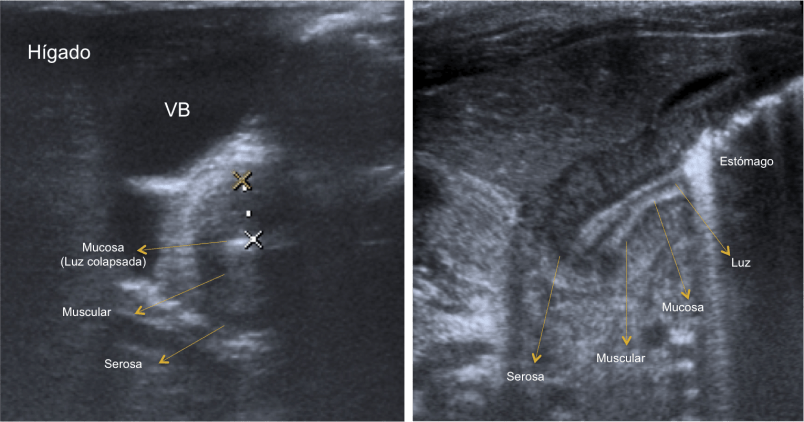

Las sondas que se deben utilizar son las lineales de entre 7-15 MHz (sondas de alta frecuencia). Estas sondas permiten identificar todas las capas de las pared del píloro. A la hora de realizar la prueba es mejor que el estómago se encuentre con poco contenido gástrico. Si el estómago esta lleno de gas se debe poner al paciente en posición oblicua anterior derecha, permitiendo que el líquido gástrico se deposite en el antro por efecto de la gravedad. Un truco es tratar de identificar en primer lugar la vesícula biliar, el píloro suele encontrarse adyacente a la misma.

El signo el doble rail se debe a que la mucosa comprimida presenta múltiples acúmulos líneales de líquido: se ven bandas de líquido hipoecogénicas con bandas hiperecogénicas tanto en visión longitudinal como transversal. En la sección transversal es típico observar la imagen en Donut o anillo hipoecoico heterogéneo con un centro hiperecogénico: el anillo hipoecogénico corresponde a la muscular engrosada, mientras que el centro hiperecogénico corresponder a la superficie mucosa redundante y edematosa.